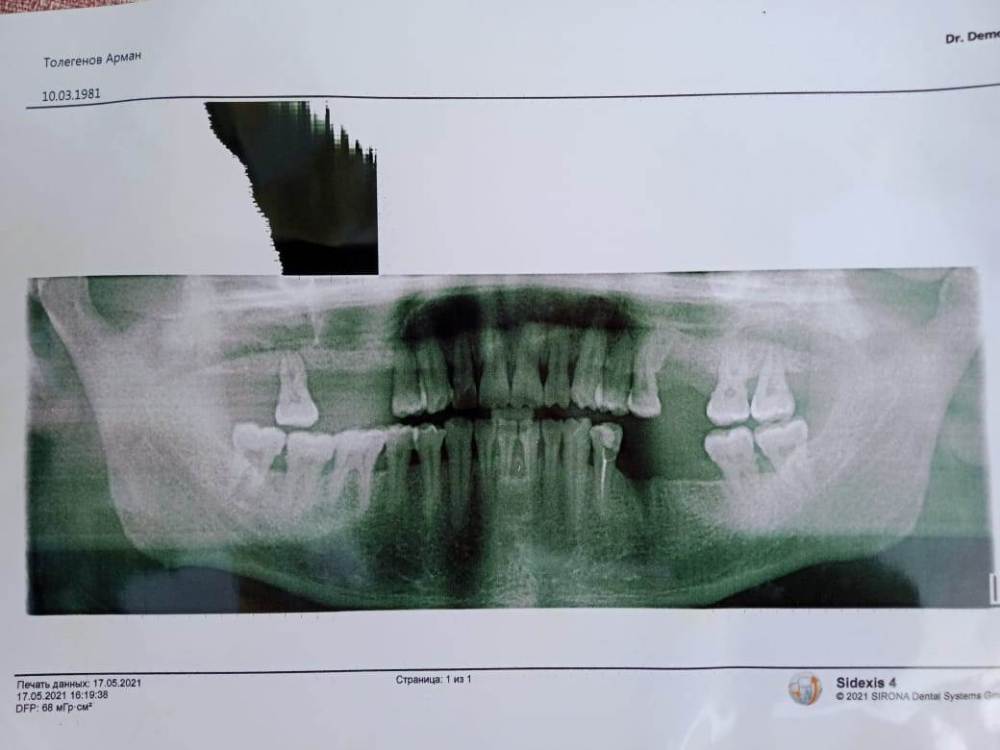

вылечили зуб и через пару месяцев начал болеть потехоньку.  пришлось оторвать зуб.  в зубе  снизу на корне была   белая   тонкая  как нить. не обратил внимание.  но  боль не перестает. и лунка  долго востанавливается так сказали хирурги  когда делал панорамный снимок  . стало еще больнее  и настолько больно  что и слово не сказать. как оторвал прошло больше 3-рех месяцев  вот и мучаюсь . симптомы такие -   когда  затягиваю сигатеру  наступает боль. боль в области 5 зуба нижней челюсти.  боль   острая  с неким ощущением холодка. думаю обратится ЧЛХ.     заранее хотел тут  узнать или проконсультироватся в чем может быть такая проблема.  если есть тут професура  и хирурги .  и еще  я растратился  просто так  на две остальный зубы  про   словам других стоматологов и пришлость удалить не те зубы а причина  в другом ... помогите найти причину.  БУдУ ОЧЕНЬ ВАМ  ВСЕМ БЛАГОДАРЕН !   эта уже  стала проблемой  в моей жизни ...

1622306037079.jpg